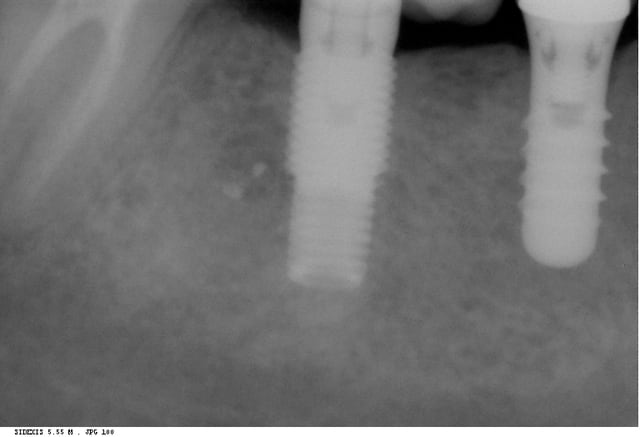

Je cherche la marque de l'implant le plus distal.

zimmer screwvent platform 4,5

bien tenté philoustre...

tu as à moitié raison...la connexion est la bonne, cad que c'est un classique hex "zimmer"....

mais, c'est pas un screwvent....(pas de trou ovale à l'apex)

c'est un minivent...

c'est bien un screw 4,5 . car c'est l'image radiologique typique quand l'axe de l'évent est perpendiculaire au rayon X.